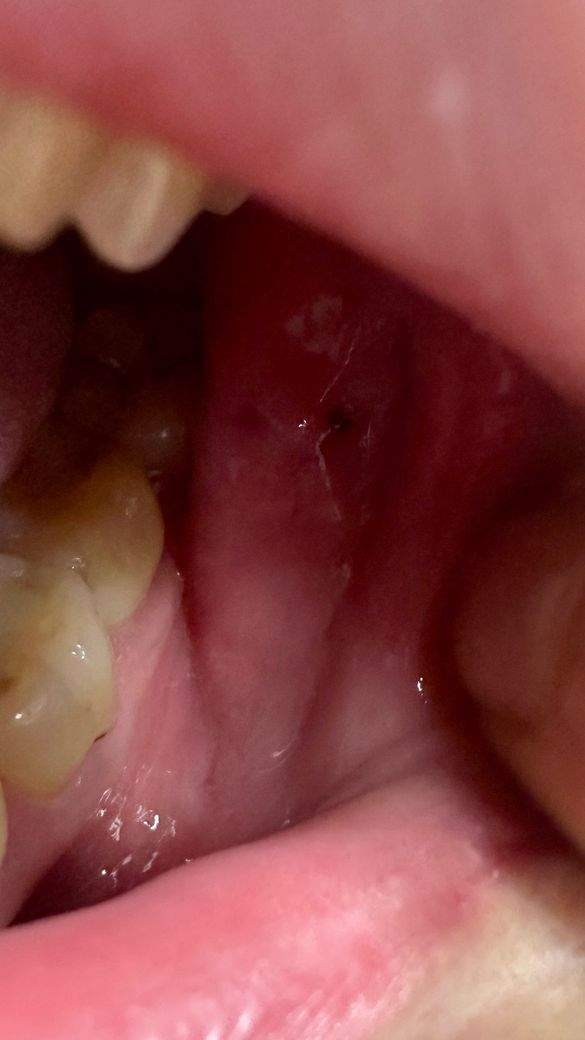

가끔씩 침에 피가나와요+입안에 검은점이있어요

입안에 비춰보니 왼쪽에 웬 검은점이보여 저게뭔가하고 여쭤봅니다

사진에 보이는건 볼살이 치아에 씹히면서 피가 고여 잇는 상태입니다. 그냥 터트리면됩니다.

양치질을 할 때 점막 조직을 너무 강하게 자극을 하면 출혈이 될 수 있습니다. 이런 경우 양치를 할 때 점막 조직을 너무 심하게 자극하는 것을 줄이는 것이 좋습니다. 사진으로 보이는 검은 점은 혈종으로 보입니다. 혈종은 점막 사이에 출입이 되면서 생기게 됩니다. 점막 조직이 외부 자극에 의해서 자극을 받았을 때 생기는 것으로 간단하게 제거할 수 있습니다.